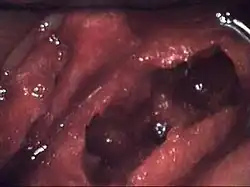

L’ostéonécrose de la mâchoire est une maladie sévère de l’os qui atteint la mâchoire, c’est-à-dire les maxillaires et la mandibule. Les lésions osseuses et la nécrose surviennent à la suite d'une réduction de l'apport sanguin local (ischémie). Cette affection entre donc dans la catégorie générale des nécroses ischémiques ou ostéonécrose avasculaire (littéralement « mort osseuse par insuffisance circulatoire »).

Les personnes ayant une ostéonécrose de la mâchoire peuvent présenter une nécrose de l’os ou de la moelle osseuse qui a été lentement asphyxiée ou privée de nutriments. L’os qui subit un déficit chronique d’apport vasculaire réagit par le développement d’une moelle fibreuse car les fibres survivent plus facilement dans des zones privées d'éléments nutritifs, soit en formant une moelle grasse nécrosée (pourriture humide), soit en formant une moelle très sèche, parfois scléreuse (pourriture sèche), ou encore un espace complètement vide dans moelle (ostéocavitation), également typique de l’ostéonécrose. La diminution du flux sanguin peut aussi être la conséquence d’un infarctus osseux, dû à la formation de caillots de sang dans les petits vaisseaux sanguins de l’os spongieux.

À la suite de nombreux accidents ischémiques des modifications pathologiques dans la moelle osseuse et les trabéculations de l’os spongieux de la mâchoire ont été documentés. Au microscope, on distingue des zones de dégénérescence graisseuse apparente et / ou de nécrose, souvent avec de la graisse provenant de la destruction de cellules adipeuses (kystes huileux) et une fibrose de la moelle (dégénérescence graisseuse réticulaire). Ces anomalies sont présentes, même si la plupart des trabéculations osseuses paraissent à première vue viables, matures et d’aspect normal, mais à y regarder de plus près, on décèle une raréfaction localisée des ostéocytes et des micro-fissures d’étendue variable (disséminées le long des plans de clivage naturels). Les caractéristiques microscopiques sont similaires à celles des accidents ischémiques ou ostéonécroses aseptiques des os longs, des ostéonécroses induites par les corticoïdes, et l'ostéomyélite de la maladie des caissons (« plongeurs en eau profonde») [6].

L'ostéonécrose peut atteindre n'importe quel os, mais les hanches, les genoux et les mâchoires sont les localisations les plus souvent concernées. La douleur peut souvent être intense, surtout si les dents et / ou une branche du nerf trijumeau sont en cause, mais de nombreux patients ne ressentent pas de douleur, au moins dans les premiers stades. Quand une névralgie faciale sévère est en cause, le terme NICO, pour Neuralgia-inducteurs Cavitational ostéonécrosis (névralgie induite par ostéonécrose cavitaire), est fréquemment utilisé.

L’ostéonécrose, même dans ses formes mineures ou atténuées, crée dans la moelle osseuse un environnement qui sera propice à la croissance bactérienne. Étant donné que de nombreuses personnes ont des infections des dents et des gencives se développant à bas bruit, c'est probablement ce qui est l'un des principaux mécanismes par lesquels le problème du faible débit sanguin dans la moelle peut s'aggraver; la moindre infection / inflammation locale va provoquer l'augmentation des pressions et favoriser la formation de caillots dans la zone concernée. Aucune autre localisation osseuse ne présente ce mécanisme qui est un facteur de risque majeur pour l’ostéonécrose. Une grande variété de bactéries ont été cultivés à partir des lésions d’ostéonécrose. Typiquement, ce sont les mêmes microorganismes, qu'on retrouve dans les parodontites ou les dents dévitalisées. Toutefois, en raison de la coloration spéciale des tissus biopsiés, les éléments bactériens sont rarement trouvés en grand nombre. Ainsi, alors que l’ostéonécrose n'est pas initialement infectée, de nombreux cas présentent secondairement ont un faible niveau d'infection bactérienne chronique et non suppurative (ostéomyélite) qui peut être associée à l’ostéonécrose. Les infections fongiques atteignant l'os ne semblent pas être un problème, mais les infections virales n'ont pas été étudiées. Certains virus, comme celui de la variole (virus qui n'existe plus dans la nature) peuvent provoquer une ostéonécrose.